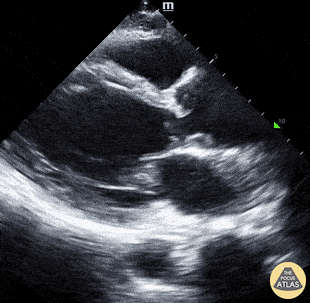

Cardiac sign seen on this PLAX view:

McConnell's sign